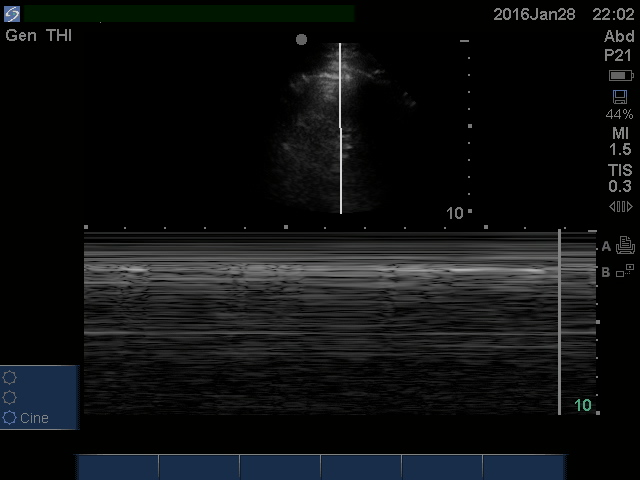

Does this patient have a pneumothorax?

This is as bread & butter as it gets… Ultrasound is far better than x-ray when you want to find a pneumothorax.  I use this most commonly in a hemodynamically UNSTABLE patient when time is the essence.  2 minute video here.